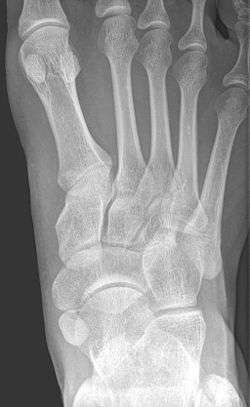

![]() X-ray of the foot showing an accessory navicular bone | |

An accessory navicular bone is an accessory bone of the foot that occasionally develops abnormally in front of the ankle towards the inside of the foot. This bone may be present in approximately 2-21% of the general population and is usually asymptomatic.[1][2][3][4] When it is symptomatic, surgery may be necessary.